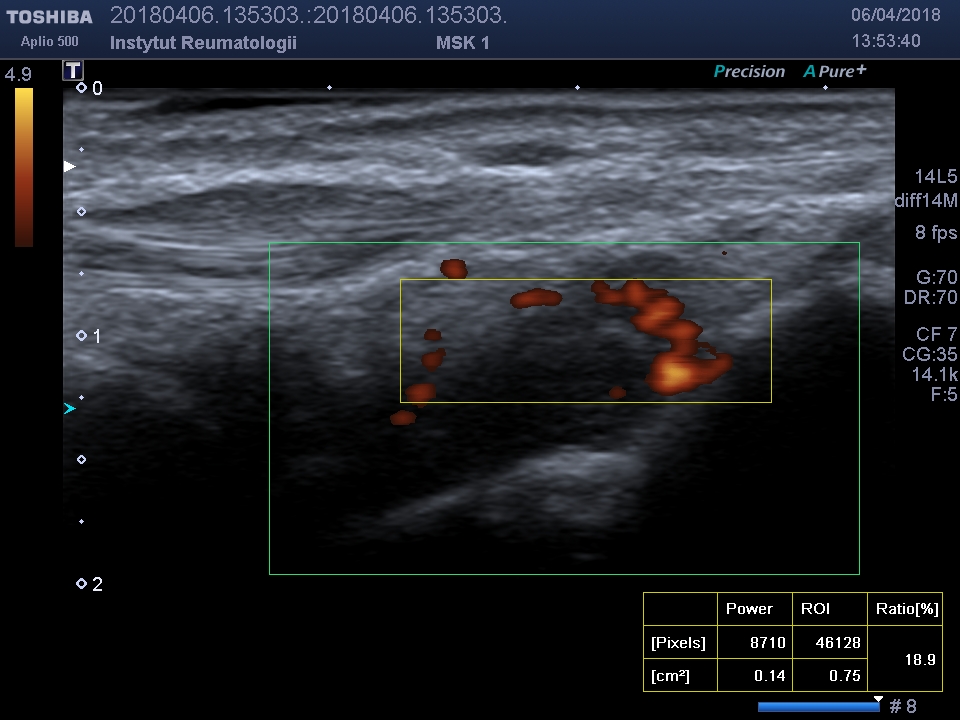

Methods: A total of n=80 patients were included into the study, n=60 with RA and n=20 PsA. Majority of them (for both group) were female (n=53.66.25%). Laboratory variables were assessed: RF (IU/ML units), ACPA (U/ML), ESR (mm/hour) and C-reactive protein (CRP;MG/L); disease activity were assessed by DAS 28(ESR) and simplified disease activity score (SDAI). The power doppler US (PDUS) was performed with assessment of a) the degree of the synovial membrane vascularization (from 0 to 4 grade); the following scores were used in the assessment: 0- no signs of synovial flow, 1- isolated signals in hypertrophied synovium, 2-vessels occupy less than 50% of hypertrophied membrane area synovitis, 3- inflammation affects over 50% of the examined area; b) vascularity index measured by PDUS index (INDEX%) in the ROI (region of interest) frame (figure 1). All patients underwent examination using the same US machine and by the same specialist in radiology and imaging diagnostics.

Synovial membrane with active inflammation (vascularization) and region of interest frame indicated.